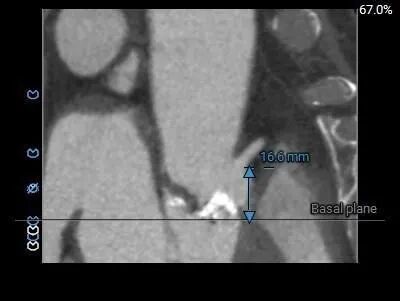

左冠12.2,右冠16.6,综合分析冠脉阻挡风险适中

左冠19.4,右冠25.8,综合分析冠脉阻挡风险适中

左冠18.8,右冠19,综合分析冠脉阻挡风险适中。